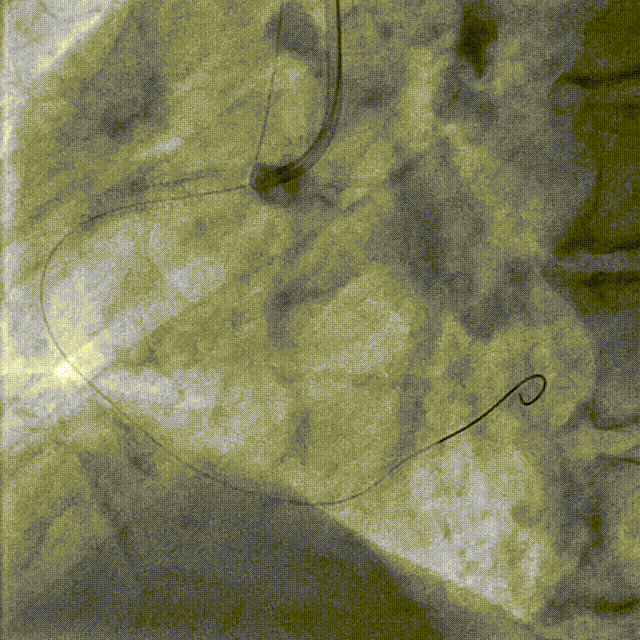

PCI-LAD TR, 7F EBU3.5

ROTA with 2.0mm burr

Angiography & Angioplasty NC 2.5*12mm

Stenting DES 2.5*24mm

Stent Optimization NC 2.5*12mm + NC 2.75*8mm

Lesion Preparation Cutting balloon 2.75*10mm @ 14atm

DCB Angioplasty DCB 2.75*25mm @ 8atm, 60s

Final Results